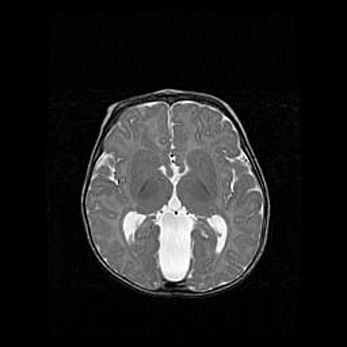

Мальформация Денди-Уокера. Киста задней черепной ямки.

Агенезия мозолистого тела.

Возраст: 2,5 месяца

Вес: 2420 г

Пол: женский

Окружность головы: 37 см

Срок гестации: 32 недели

Мальформация Денди—Уокера — редкий вид патологии ЦНС, представляющий собой врожденный порок развития каудального отдела ствола и червя мозжечка, ведущий к неполному раскрытию срединной (Мажанди) и латеральных (Лушка) апертур IV желудочка мозга. Для этогно синдрома характерна триада симптомов: гипотрофия червя мозжечка и/или полушарий мозжечка, кисты задней черепной ямки, гидроцефалия различной степени. В 70% случаев порок сочетается и с другими аномалиями головного мозга, в частности с агенезией мозолистого тела.